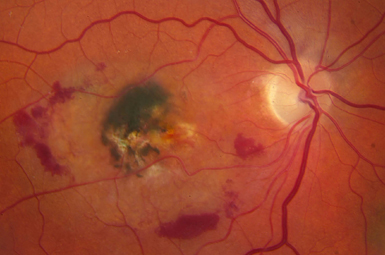

Macular Degeneration

There are two types of Macular Degeneration – Wet and Dry. If it becomes Wet, early intervention can usually preserve sight.